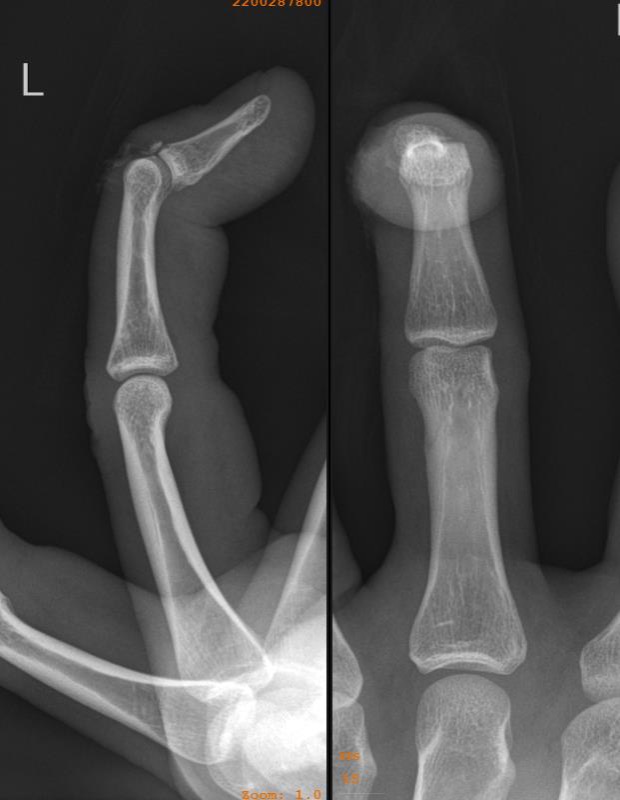

2. Bony fracture

![]()

Drop finger / extension lag of the DIPJ

- volar subluxation of distal phalanx

- fragment > 50% joint surface